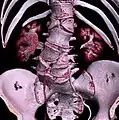

Sacralization of the L5 vertebra is seen at the lower right of the image.

Sacralization of the fifth lumbar vertebra (or sacralization) is a congenital anomaly, in which the transverse process of the last lumbar vertebra (L5) fuses to the sacrum on one side or both, or to ilium, or both. These anomalies are observed in about 3.5 percent of people, and it is usually bilateral but can be unilateral or incomplete (ipsilateral or contralateral rudimentary facets) as well. Although sacralization may be a cause of low back pain, it is asymptomatic in many cases (especially bilateral type). Low back pain in these cases most likely occurs due to biomechanics. In sacralization, the L5-S1 intervertebral disc may be thin and narrow. This abnormality is found by X-ray.

Sacralization of L6 means L6 attaches to S1 via a rudimentary joint. This L6-S1 joint creates additional motion, increasing the potential for motion-related stress and lower back pain/conditions. This condition can usually be treated without surgery, injecting steroid medication at the pseudoarticulation instead. Additionally, if L6 fuses to another vertebra this is increasingly likely to cause lower back pain. [3] The presence of a sixth vertebra in the space where five vertebrae normally reside also decreases the flexibility of the spine and increases the likelihood of injury. [4]